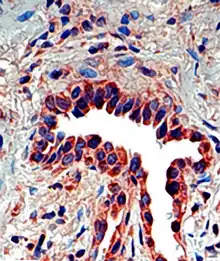

Osteopontin is expressed in a variety of tissue types including cardiac fibroblasts,[25] preosteoblasts, osteoblasts, osteocytes, odontoblasts, some bone marrow cells, hypertrophic chondrocytes, dendritic cells, macrophages,[26] smooth muscle,[27] skeletal muscle myoblasts,[28] endothelial cells, and extraosseous (non-bone) cells in the inner ear, brain, kidney, deciduum, and placenta. Synthesis of osteopontin is stimulated by calcitriol (1,25-dihydroxy-vitamin D3).